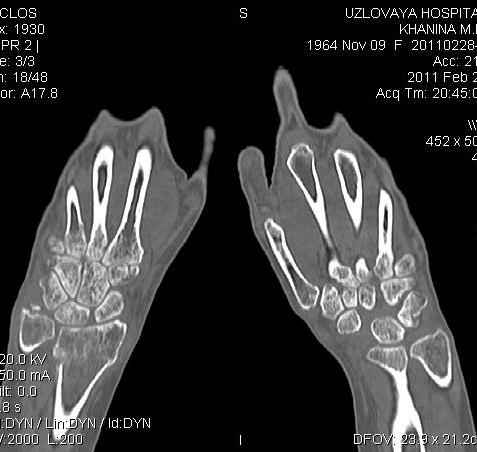

Уважаемые коллеги.Прошу обсудить случай лечения перелома дистального метаэпифиза лучевой кости. Ситуация скандальная и крайне неблагоприятная. Больная с патологической обстоятельностью мышления, склонностью к сутяжничеству, патологическими умозаключениями, не поддающимися коррекции (см. психиатрию, правда офиц. диагноза нет). В данном случае есть ряд ошибок с нашей стороны, прежде всего в отношении качества ведения документации (за что получил административное взыскание, по делом мне дураку). В остальном- придерживались в лечении подхода классический советской школы. Так как умную операцию…… сами знаете… 15.12- перелом луча в Москве. Там же репозиция, гипс. Дальнейшее лечение у нас в ЦРБ. 20.12.- вторичное смещение в гипсе21.12- под внутривенным наркозом- репозиция, гипсовая лонгета. Дальше начинается самое интересное. После репозиции больная заявила, что я (репозицию делал я) порвал ей все связки в суставе, посинел у нее 5 палец, якобы я за него тянул и т. д. На самом деле на 2 сутки после репозиции рука немного отекла и было незначительное сдавление гипсом, который был ослаблен. Дальнейшее лечение консервативное. Через 6 недель- гипс снят, назначено ЛФК. Пациентка крайне недовольна. Говорит, что на снимке у нее выступает кость, я ей сломал руку и.т.д. В общем началось. Пациентка прочитала в интернете наверное все, что есть по данной травме.По заключениями рентгенологов и консультанта из КДЦ областной больницы - стояние отломков допустимое. Объективно говоря- снижена высота лучевой кости, диастаз лучелоктевого сочленения, и не сросся шиловидный отросток. однако на РКТ при сравнении с другой стороной- разница незначительная. Дальше в одной из больниц нашей области и одной из больниц Москвы (вроде бы КГБ 53) врачи сказали, что репозиция сделана плохо. Нужна операция (восстановить длину лучевой кости), даже один из них предложил РЕДРЕССАЦИЮ (хи-хи) с наложением аппарата Илизарова. Что это для данной больной- радость неописанная. (см. описание психического статуса). Ничем другим, кроме зарабатывания дешевого авторитета объяснить данный факт не могу.Кстати, у больной еще нейропатия локтевого нерва.Для разрешения конфликта больная направлена на консультацию в ЦИТО на 03.03.11.

2. По сравнению и без ! втор смещение незначительное.НЕТ НИКАКОЙ ,,локтевой косорукости,,маделунгов . но имеется смещение совести у врачей КГБ 35--НЕТ ЗДОРОВЫХ, есть только недообследованные ! Этому смещению аппарат внешней фиксации не поможет .Психопаткам в менопаузе да весной только этого и надо чуть толкнули и поехало .

Я прекрасно знаю, что укорочение лучевой кости более 2 мм требует оперативного лечения с целью восстановления её длины, и что некоторые выполняют рефиксацию шиловидного отростка. (благо на последнем симпозиуме АО я присутствовал)

2.Укорочение лучевой кости и лучелоктевой диастаз невелики,но отрицать их клиническую значимость весьма сложно.

3.Исходя из конкретной ситуации и здравого смысла абсолютных показаний к операции не было и сразу после травмы и нет сейчас ,уже после сращения,поскольку перелом внесуставной,а осколок по тылу луча не препятствует торцевому упору по волярному краю луча.